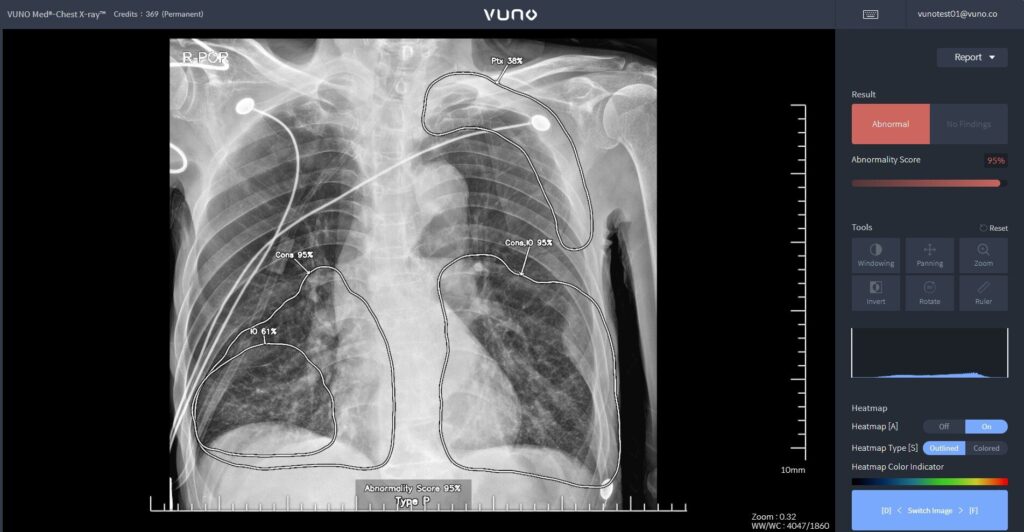

「VUNO(ビューノ)」のAIベースの胸部X線読み取りソリューション「VUNO Med®-Chest X-ray™」使用画面(出典:VUNO)